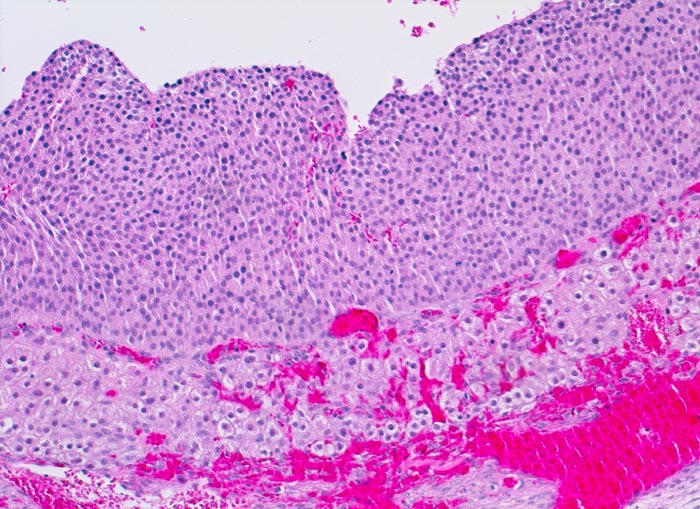

PathoPic ID 4390 - Rupturierter Follikel

Rupturierter Follikel

Normalbefund

Ovar

Genitalorgane, weiblich

Zum Follikellumen hin eine breite Schicht von kleinen Granulosazellen. Gegen aussen folgt die stark vaskularisierte Theca interna mit grösseren luteinisierten Zellen.

Histologie

100